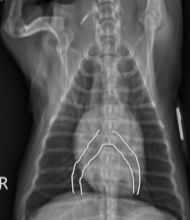

What sign is this?

Bowlegged Cowboy Sign - L. atrial enlargement